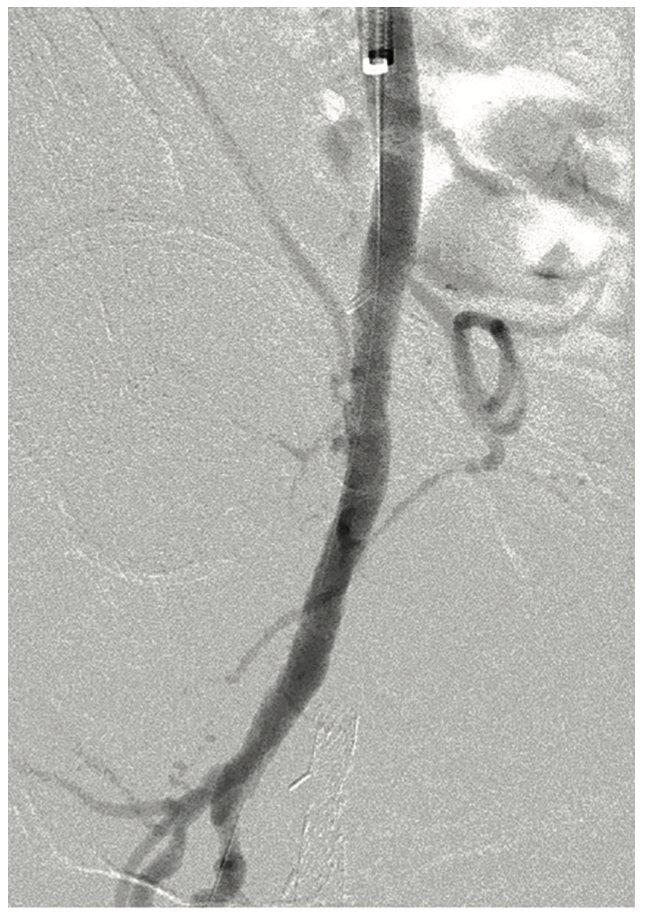

A formal right lower extremity arteriogram was subsequently performed and revealed a critical stenosis of the distal common femoral artery and proximal PFA (Figure 1). The SFA was occluded to its ostia and the proximal aspect of the stent was found to be fractured. There was reconstitution of the P3 portion of the popliteal artery and runoff to the foot via a patent but moderately diseased peroneal and posterior tibial artery. The femoral bifurcation lesion was further evaluated with intravascular ultrasound (IVUS), which revealed a concentric 88% stenosis composed of primarily soft plaque (Figure 2A).

To execute this strategy, a 7 French, 45 cm sheath was placed over the aortic bifurcation and positioned in the very proximal common femoral artery. The patient was anticoagulated with heparin 80 units/kg intravenously. A 6 mm SpiderFX embolic protection device (EPD) (Medtronic) was placed in the largest first-order branch of the PFA and a magnified road map of the lesion was created at 25 degrees right anterior oblique (RAO). A HawkOne LS directional atherectomy device (Medtronic) was selected for its larger plaque excision capability and its shorter nose cone, given the short length of the lesion, and a desire to keep the EPD closer to the lesion and thereby protect more branches (Figure 3). A series of six initial passes with the device at 1-2mm per second was made in a uniform, radial manner. Subsequent angiography demonstrated a marked reduction in stenosis and an additional 5-6 passes were made in a targeted fashion at remaining locations of visible disease. With less than 30% stenosis remaining, an In.Pact DCB (6 mm x 40 mm) (Medtronic) was selected based upon IVUS measurements and inflated to nominal pressure for three minutes (Figures 4-5). Follow-up angiography demonstrated <20% residual stenosis with no evidence of dissection or distal embolization (Figure 6). These findings were confirmed by final IVUS imaging and the procedure was completed without complication (Figure 2B). The arteriotomy was closed by Perclose (Abbott Vascular) and the patient was ambulatory two hours after the procedure. Dual antiplatelet therapy was prescribed for three months following the procedure and low-dose aspirin indefinitely.